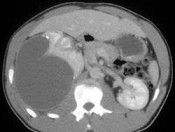

- 单项选择题患者19岁,肾性高血压, 根据图像,对其原因的评价, 正确的诊断为 ( )

A、嗜铬细胞瘤

B、肾动脉狭窄

C、肾癌

D、Page(佩奇氏)肾

E、以上都不是